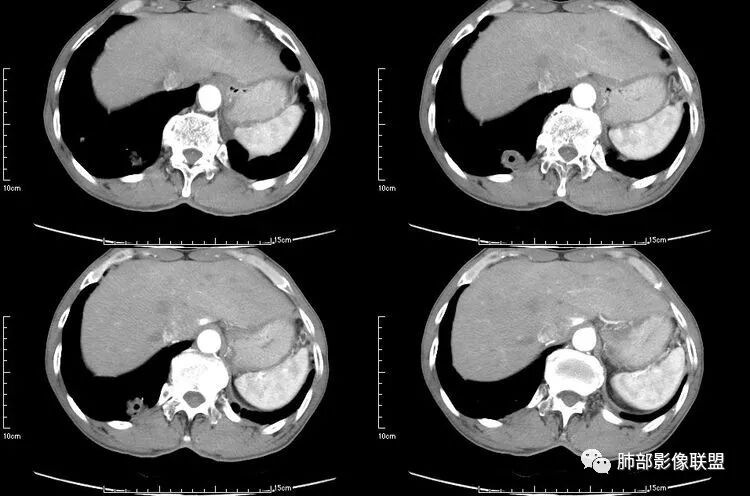

患者老年男性,咳嗽、咳痰、痰中带血伴胸闷2月余。长期大量吸烟史。查肝肾功能、血糖、血脂、心肌酶、电解质、血沉、C反应蛋白、抗“O”、类风湿因子、抗核抗体谱无明显异常。肿瘤标志物提示NSE、CYFRA21-1稍升高。胸部CT:肺气肿背景,左肺下叶后基底段不规则肿块影,见支气管截断,内见大片状低密度区及部分血管影,增强轻度强化,远端空洞形成。双肺多发不规则实性结节影、见毛刺、胸膜牵拉及血管集束,结节内见空洞形成,部分可见血管影,多位于胸膜下。双肺见多发肺大泡。综合考虑左下肺恶性病变并双肺转移。鳞癌或淋巴瘤可能。鉴别血管炎性病变及真菌感染。

无发热,其他慢性细菌先不考虑,有的低毒的,但是结节形态还是比较不规则的,分布也是比较随机,更像原发病灶。真菌方面,结节没有融合,坏死也是液化坏死,不符合隐球菌,曲霉不符合IPA,慢性吸入的也少见。结核没有树丫,不考虑。鉴别主要是GPA,和肺癌。GPA不支持点是皮肤,肾脏没有累及,ANCA不支持。。。肺癌主要是腺癌和鳞癌转移。比较支持的是淋巴结肿大,和左下肺的主病灶,支气管堵塞和异常强化。还有分叶,局部膨隆。可以建议支气管镜检测。